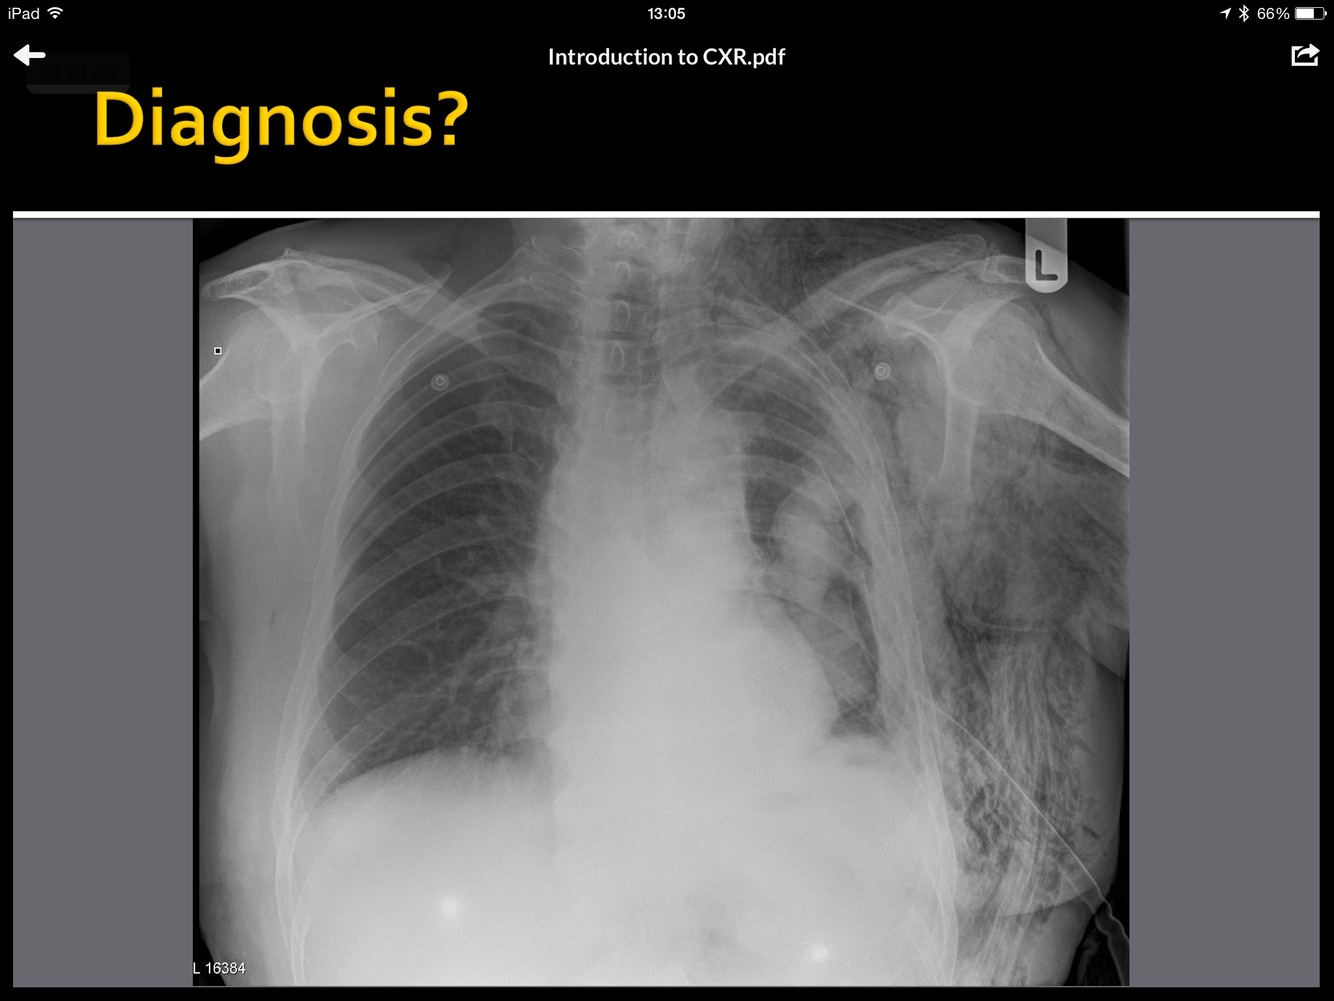

What is the pathology here?